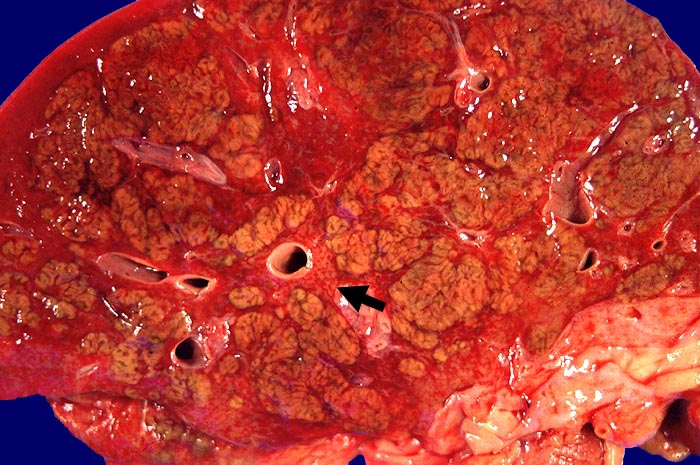

Makroskopie

Befund

Pathologischer Befund